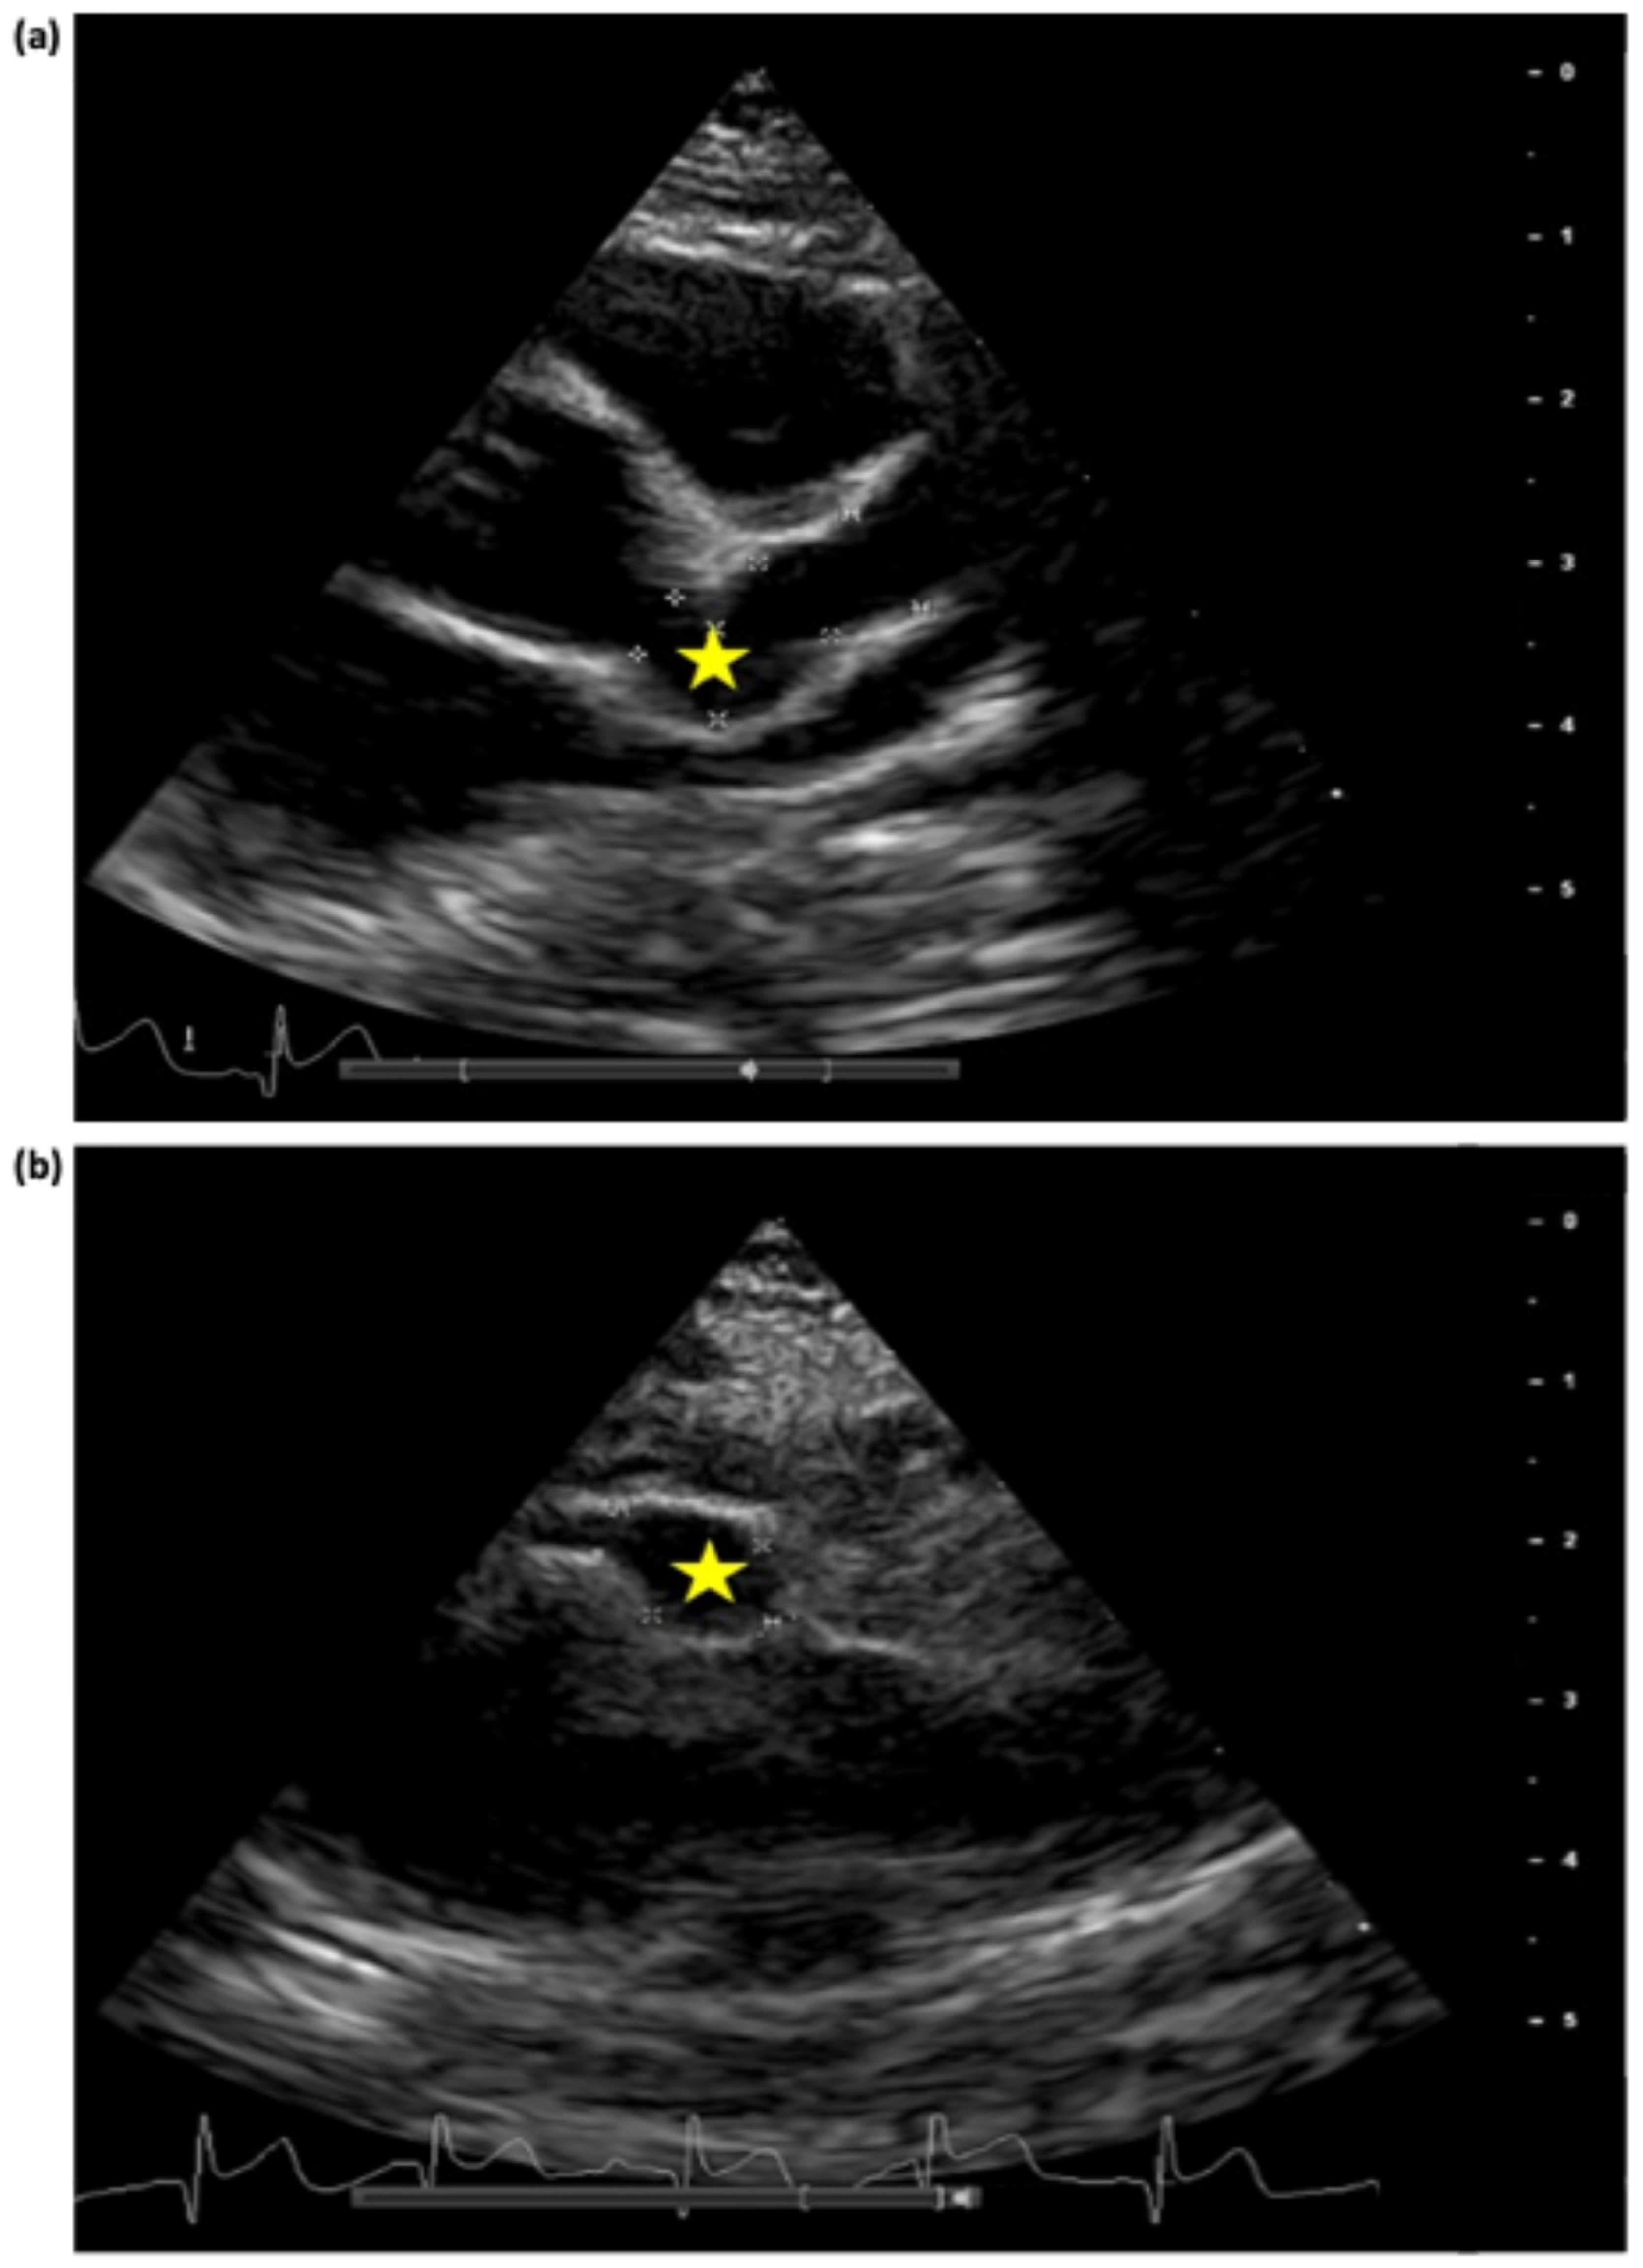

| LMCA | Ø | 1st 4 mm (z-score +5.8) | 1st 4.2 mm (z-score +6.4) | 1st 4.5 mm (z-score +7.2) | 1st 4 mm (z-score +5.8) | Ø | Ø | Ø |

| Ø | 2nd 6 mm (z-score +11.4) | 2nd 5.3 mm (z-score +9.4) | 2nd 5.5 mm (z-score +10) | |||||

| LAD | 1st 4.2 mm (z-score +12) | 1st 5 mm (z-score +16) | 1st 5.5 mm (z-score +18) | 1st 5.5 mm (z-score +18) | 1st 5.5 mm (z-score +18) | 1st 5.4 mm (z-score +17.8) | 2 aneurysms max diameter 4.5 mm (z-score +13.7) | 1st 3.6 mm (z-score +9.6) |

| Ø | 2nd 4.4 mm (z-score +13) | 2nd 7 mm (z-score +25) | 2nd 7.5 mm (z-score +27) | 2nd 6.8 mm (z-score +24) | 2nd 6.6 mm (z-score +23) | Ø | ||

| Ø | Ø | 3rd 6 mm (z-score +20.5) | 3rd 6 mm (z-score +20.5) | Ø | Ø | Ø | Ø | |

| RCA | 1st 3.1 mm (z-score +5.5) | 1st 5.2 mm (z-score +12.5) | 1st 5.5 mm (z-score +13.5) | 1st 6.8 mm (z-score +17.8) | 1st 7 mm (z-score +18.5) | 5.4 mm (z-score +13) | Max diameter 3.4 mm (z-score +6.5) | 1st 3.5 mm (z-score +6.8) |

| Ø | 2nd 3.2 mm (z-score +6) | 2nd 4.1 mm (z-score +8.8) | 2nd 3.9 mm (z-score +8) | Ø | Ø | Ø | Ø | |